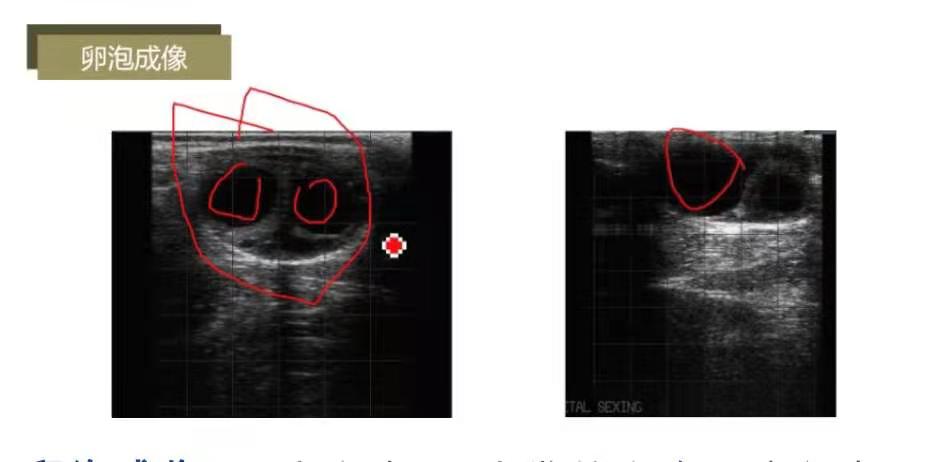

子宫成像:青年牛子宫角直径1.5-2cm,灰色;成母牛子宫角直径2-4cm;发情牛一侧子宫角开张,子宫内膜增生,发情时子宫颈口和阴道分泌粘液,流入子宫,子宫角呈现黑色。

卵巢成像:卵巢灰色,黑色为卵泡内液体;因无卵泡,显示灰色;含2个卵泡。

卵泡成像:2个卵泡;1个发情卵泡,直径在2cm左右。